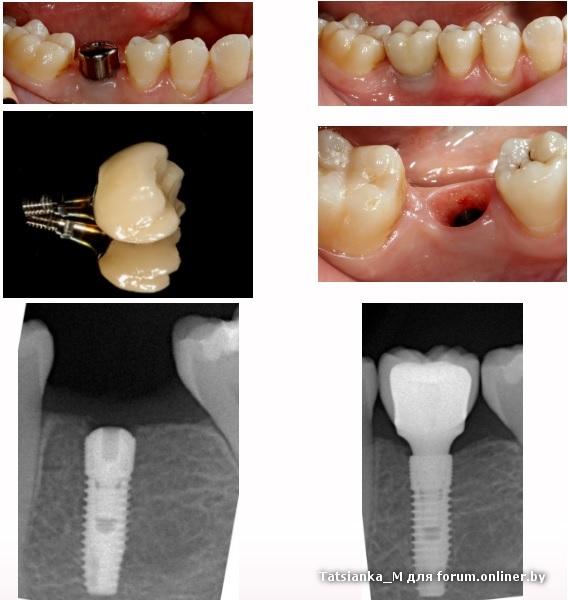

Данный вариант имплантации моляра считается хорошим по эстетике? Эту работу приводят на сайте одной из клиник в качестве образца (=лучшей из лучших) клиенту...

Смущает многое: зуб не совсем ровно стоит в ряду, гораздо меньше в размерах, чем должна быть шестерка, имеет некрасивое тонкое основание (наверняка еще и неудобное в эксплуатации, кажется, что там будут собираться немалые запасы пищи после обеда), и имплант просвечивает из-под десны.

Есть ли технологии, позволяющие реализовать имплантацию крупных жевательных зубов (6-е,7-е) так, чтобы они выглядели как свои натуральные? Красивое широкое основание у десны? чтобы зуб не смотрелся конусообразным. Чтобы был как соседняя семерка рядом с имплантом.

Tatsianka_M, ширина "прорезывания" делается (расширяется) с помощью индивидуального абатмента (стандартный абатмент узкий и получается картина зауженного зуба к десне)

Жевательная поверхность зуба на импланте делается меньше жевательной поверхности настоящего зуба, чтобы снизить немного нагрузку на имплант.

Формирование контура прорезывания индивидуальным абатменом, подсадка десневого трансплантата. Имплант+ стандартный абатмен + коронка мк стоит 500$. Если делать идеально, то имплант+ индивидуальный абатмен, коронка цирконий, такая работа уже будет от 1000$ и выше.

Типа этого

Tatsianka_M:Данный вариант имплантации моляра считается хорошим по эстетике? Эту работу приводят на сайте одной из клиник в качестве образца (=лучшей из лучших) клиенту...

что касается этой работы, то в пределах этих условий она еще достаточно не плохо сделана. 7ка наклонена, по этому ее еще нужно вкладкой покрыть, что бы выровнять с коронкой на импланте. Пациент лет нанадцать ходил без зуба.

Если бы мне такую работу сделали, мне было бы нормально, чем переплачивать 500$ за "передай привет другому стоматологу". Потому что никто из окружающих такую работу не заметит, если только не открыть рот как лошадь и показывать пальцем, какой стоматолог негодяй))), что сделал мне так некрасиво.